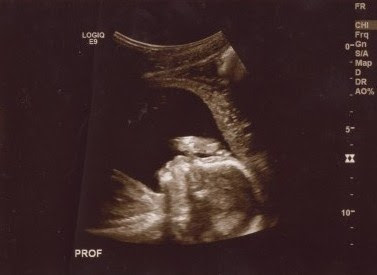

For an hour and a half today we watched, smiled, and cried at the images of our sweet baby boy. I learned a new kind of love today and my heart is full. I can't get enough of his little profile. We are so very blessed. Meet our little guy: